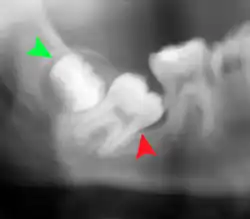

For partially impacted teeth in those over 20 year of age, the most common pathology seen, and the most common reason for wisdom teeth removal, is pericoronitis or infection of the gum tissue over the impacted tooth. The bacteria associated with infections include Peptostreptococcus, Fusobacterium, and Bacteroides bacteria. The next most common pathology seen is cavities or tooth decay. Fifteen percent of people with retained wisdom teeth exposed to the mouth have cavities on the wisdom tooth or adjacent second molar due to a wisdom tooth. The rate of cavities on the back of the second molar has been reported anywhere from 1% to 19% with the wide variation attributed to increased age.[12]

There is no standard to screen for wisdom teeth. It has been suggested, absent evidence to support routinely retaining or removing wisdom teeth, that evaluation with panoramic radiograph, starting between the ages of 16 and 25 be completed every 3 years. Once there is the possibility of the teeth developing disease, then a discussion about the operative risks versus long-term risk of retention with an oral and maxillofacial surgeon or other clinician trained to evaluate wisdom teeth is recommended. These recommendations are based on expert opinion level evidence.[19] Screening at a younger age may be required if the second molars (the "12-year molars") fail to erupt as ectopic positioning of the wisdom teeth can prevent their eruption. Radiographs can be avoided if the majority of the tooth is visible in the mouth.